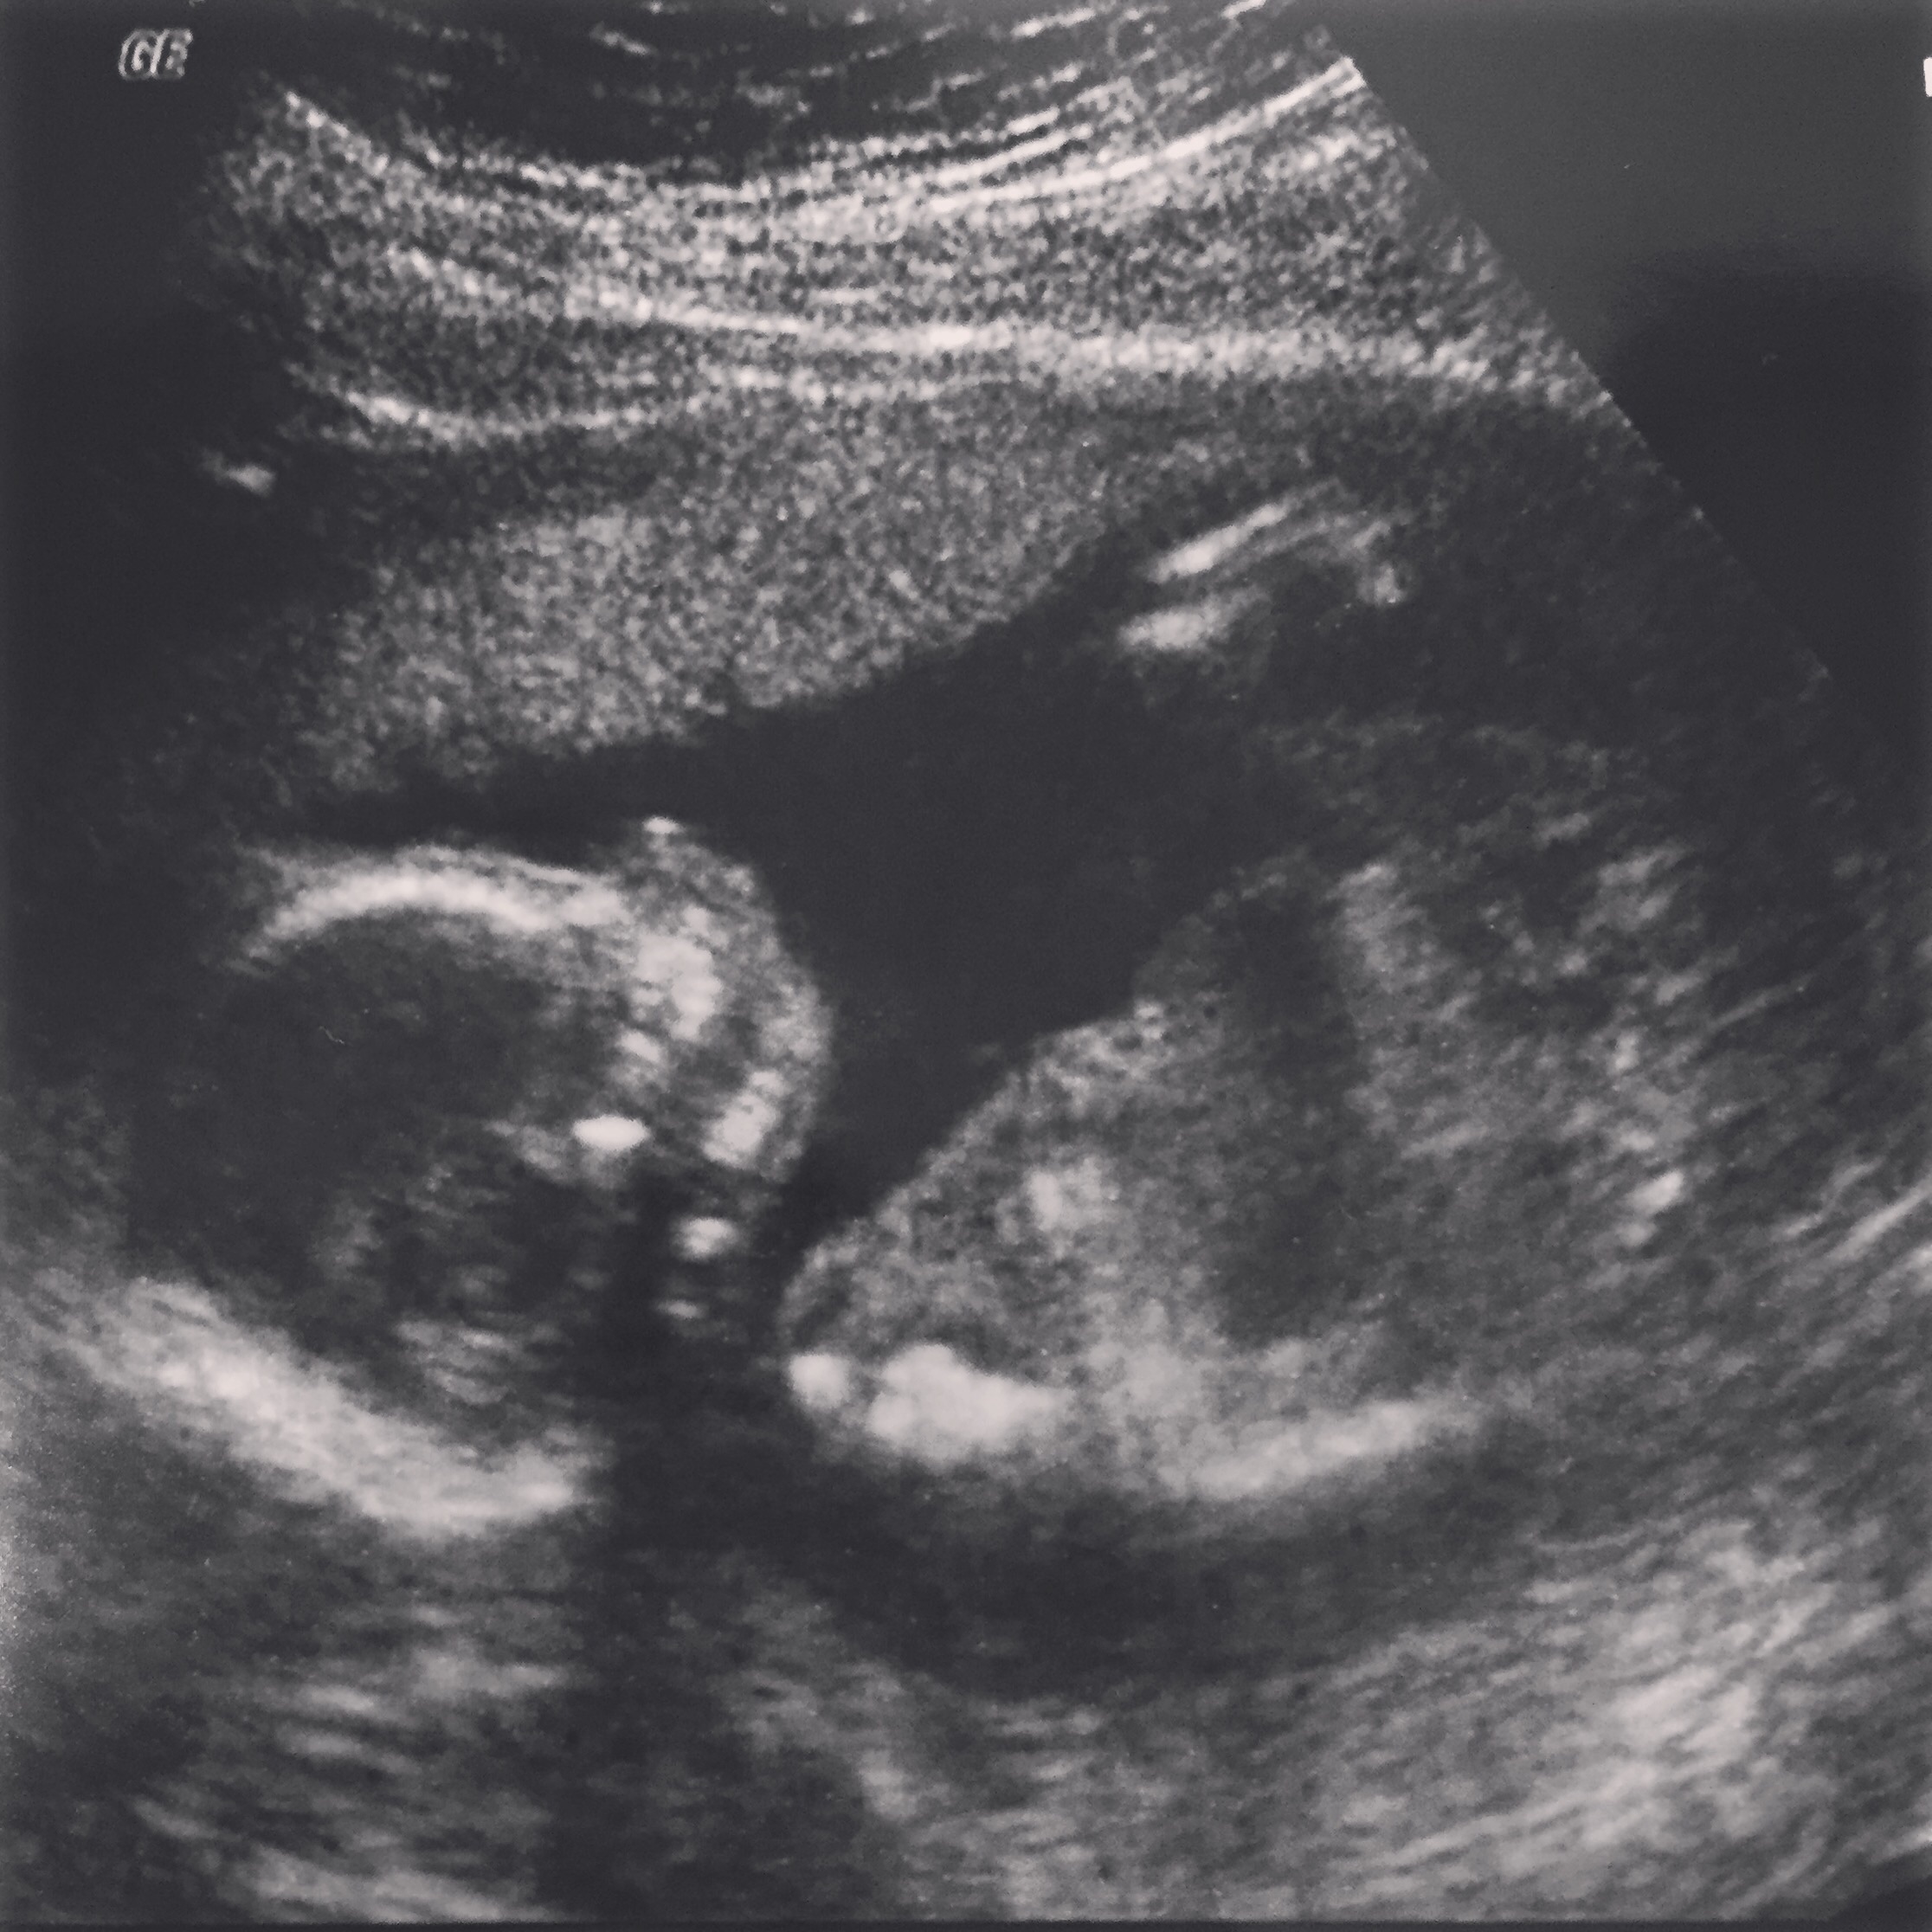

Yay for team blue! We just found out yesterday at our 20 week ultrasound appt! Everything is looking good so far. We are so thankful! I can't wait to meet him! Due Sept 10!